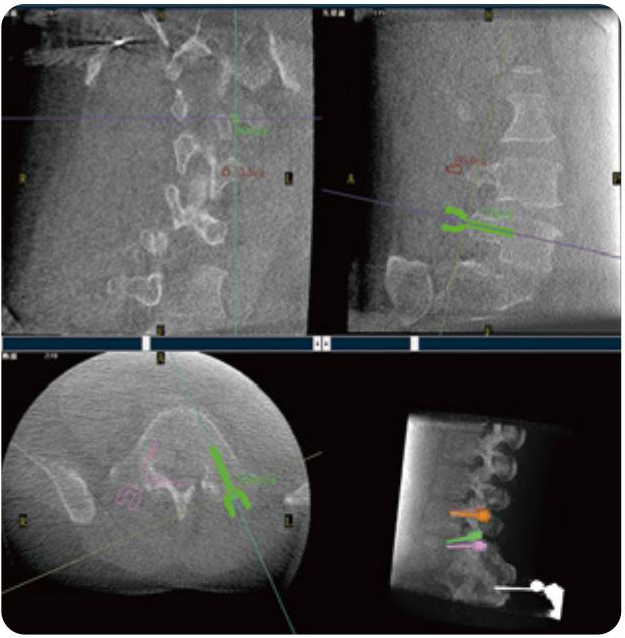

PL300B可應(yīng)用于多節(jié)段脊柱外科手術(shù),輔助醫(yī)生定位病灶部位,為脊柱外科手術(shù)(經(jīng)皮椎體成形術(shù)、椎弓根螺釘內(nèi)固定術(shù)等術(shù)式)提供術(shù)前手術(shù)流程規(guī)劃、入釘位置、角度可視化引導(dǎo),模擬仿真入釘輔助。

PL300B搭配普愛醫(yī)療自主研發(fā)生產(chǎn)的平板3D C形臂,借助一體化自適應(yīng)配準(zhǔn)( 軌跡配準(zhǔn))技術(shù),通過追蹤C(jī)形臂三維采集軌跡,自動(dòng)完成圖像坐標(biāo)建立和系統(tǒng)坐標(biāo)配準(zhǔn)。配準(zhǔn)精度更高,操作步驟少,系統(tǒng)運(yùn)作效率高。